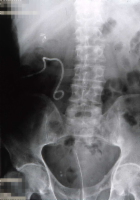

Als Komplikation ausgedehnter Mündungsdivertikel kommt es zu Abflussbehinderungen mit entsprechender Beeinträchtigung der Nierenfunktion. Als Beispiel die Harnstauungsniere bei einem Erwachsenen mit Abflussbehinderung durch ein ausgedehntes Mündungsdivertikel. Zunächst Harnableitung, dann Divertikelabtragung und Reimplantation (Abbildung HG1).

d